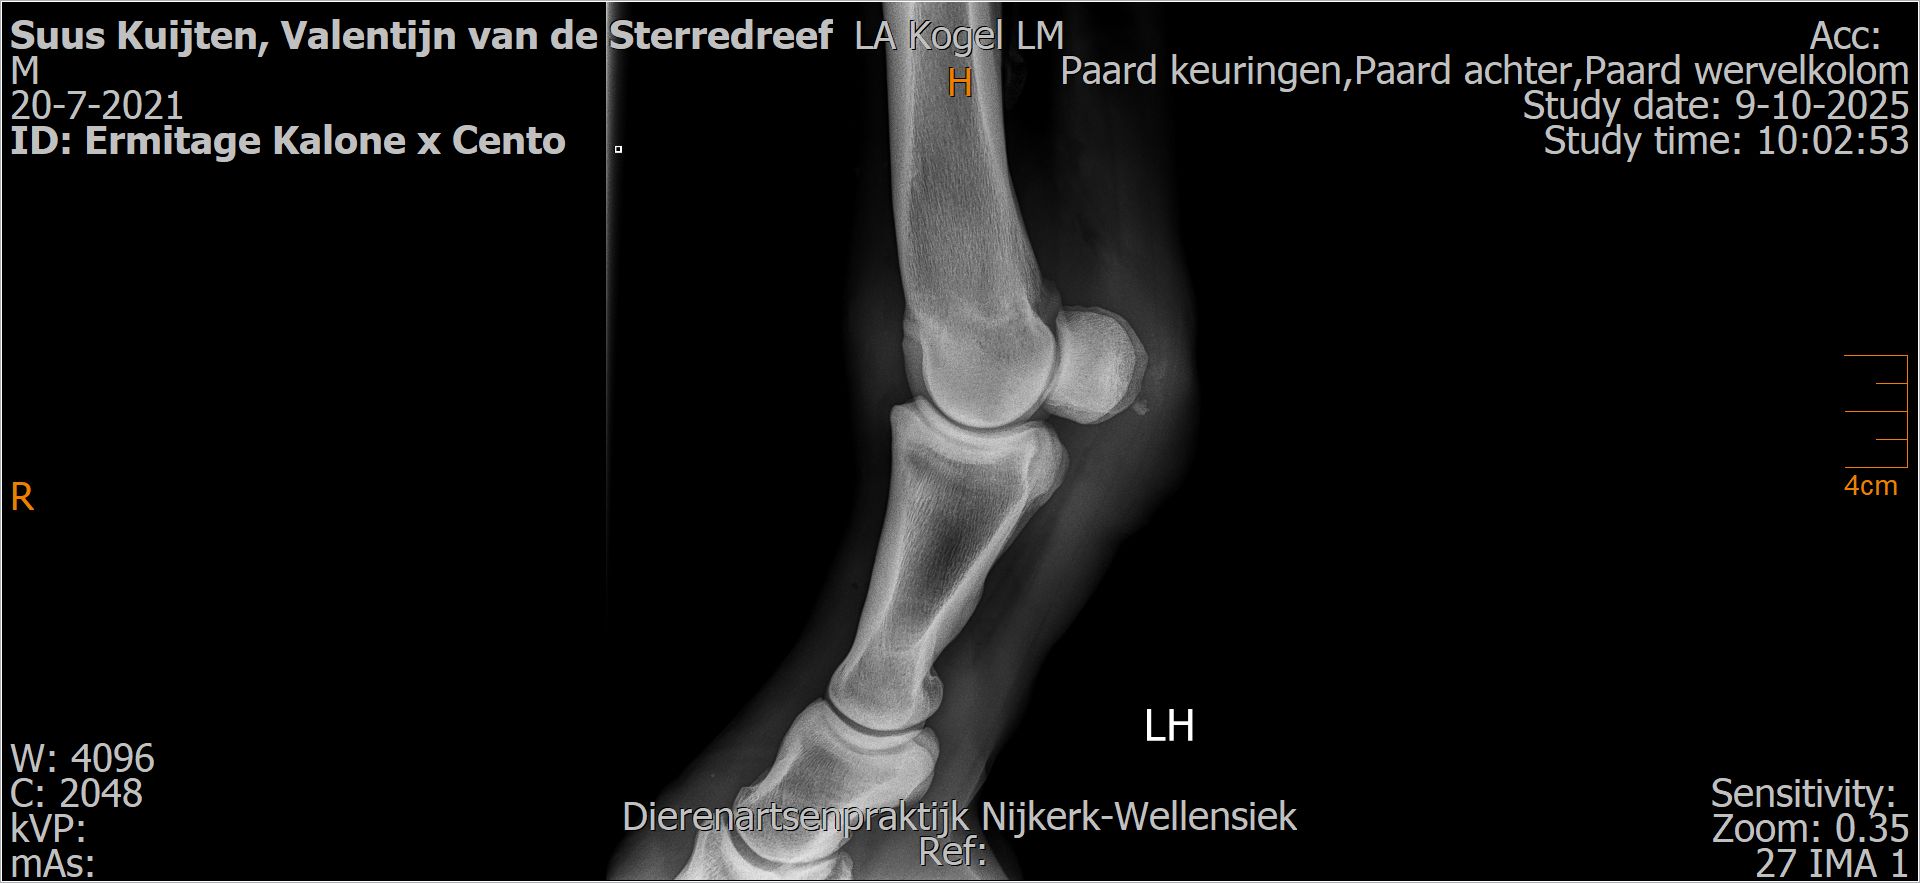

Valentijn van de Sterredreef

Leeftijd:

4

Röntgenfoto’s